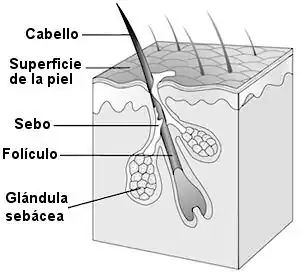

El folículo piloso es la parte de la piel que da crecimiento al cabello al concentrar células madre, formándose a partir de una invaginación tubular. Cada cabello descansa sobre un folículo piloso, siendo este, la estructura cutánea más dinámica y una de las más activas de todo el organismo.

Dentro de los folículos existen glándulas sebáceas, destinadas a la producción del sebo que lubrica la superficie del cabello. Estas se sitúan en la dermis media y están formadas por células llenas de lípidos que se desarrollan embriológicamente en el cuarto mes de gestación. Esta secreción glandular es de carácter continuo, drenando desde los acinos al conducto sebáceo principal que va a desembocar en el canal piloso.[1]

En la base del cabello, una fina red de vasos sanguíneos forma la raíz del mismo, alrededor de la cual hay una estructura blanca llamada bulbo, que es la región proliferativa. El bulbo se compone de dos o tres capas de células basales precursoras de los elementos celulares que emigrarán a la superficie por el interior de la vaina externa. En la parte inferior se hallan las células germinativas que se diferencian en anillos concéntricos celulares. Los tres anillos externos producirán las capas de la vaina pilosa interna y los tres anillos internos darán lugar al futuro cabello.

En la base del folículo hay una estructura pequeña con forma de cono llamada papila que es donde tienen origen las células que forman parte del cabello. La papila dérmica está formada por las células fibroblásticas y es la responsable del control del ciclo piloso.

El músculo erector del pelo se origina de la dermis adyacente al folículo piloso. Tiene una dirección oblicua y se inserta en las papilas dérmicas. Este músculo, al contraerse, produce la elevación del vello.

Las glándulas sudoríparas apocrinas están formadas por un gran lóbulo secretor y un conducto excretor dérmico que desemboca en el folículo pilo-sebáceo y se encuentran en las zonas de mayor vello corporal como las axilas, el área genital y el cuero cabelludo.[2]

El folículo piloso es la parte de la piel que da crecimiento al cabello al concentrar células madre. Dentro de los folículos existen glándulas sebáceas, destinadas a la producción del sebo que lubrica la superficie del cabello y que están distribuidas por toda la superficie de la piel con excepción de las palmas de las manos, plantas de los pies, etc. A mayor grosor del cabello, más glándulas sebáceas se encontrarán. En la base del cabello, una fina red de vasos sanguíneos forma la raíz del mismo. Alrededor de esta hay una estructura blanca llamada bulbo, visible al arrancar cabellos sanos.

Junto al folículo, existe un diminuto grupo muscular llamado musculus erector pili que es responsable de la perpendicularidad del cabello a la superficie de la piel, y causante de la proyección del folículo ligeramente por encima de la superficie cutánea, fenómeno conocido como piel de gallina.[3]